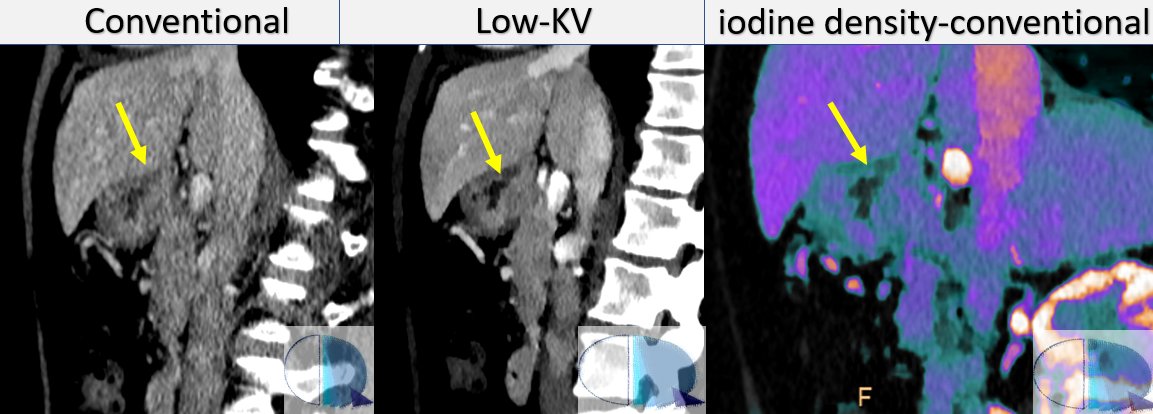

Gopal Punjabi Companion case seen the other day at RM y TC Rosario. Posterior gastric ulcer in a proven gastric neoplasm, better seen in the low-KV images and in the iodine overlay than on the conventional images. Eliseo Vañó Antonio Castellaccio #FOAMed #SpectralCT

<a href="/CtSpectral/">Gopal Punjabi</a> Companion case seen the other day at <a href="/RMyTC_Rosario/">RM y TC Rosario</a>. Posterior gastric ulcer in a proven gastric neoplasm, better seen in the low-KV images and in the iodine overlay than on the conventional images. <a href="/eliseovano/">Eliseo Vañó</a> <a href="/CastellaccioDr/">Antonio Castellaccio</a> #FOAMed #SpectralCT